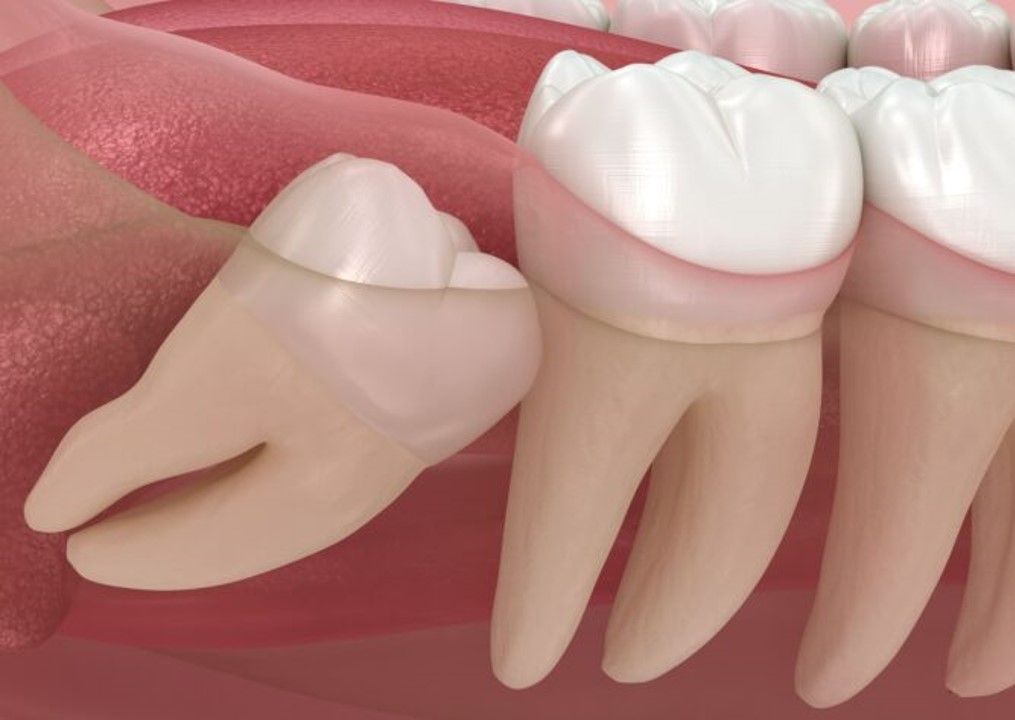

Terceros molares o muelas del juicio

Durante la salida de estas piezas dentales, por falta de espacio, muchas veces no se logra su erupción completa debido a una enquistación, lo cual puede generar dolores o molestias en el paciente.

Para evitar infecciones, quistes foliculares o diversos dolores en el paciente, se sugiere la extirpación de las muelas del juicio.